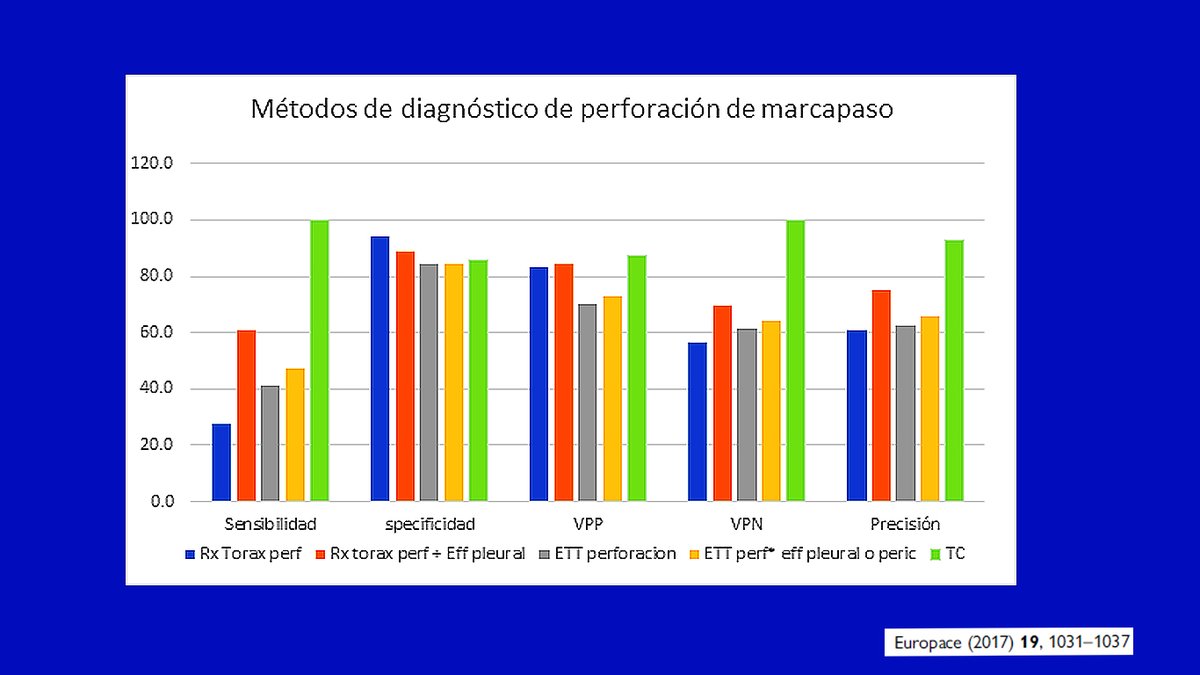

Is this a common finding?, with echo sensit 41%, spec 87% in EUROPACE 2017 (19): 1031-1037.

Diagnosis and management of iatrogenic cardiac perforation caused by pacemaker and defibrillator leads

Diagnosis and management of iatrogenic cardiac perforation caused by pacemaker and defibrillator leads

So: not so common finding with echocardiogram